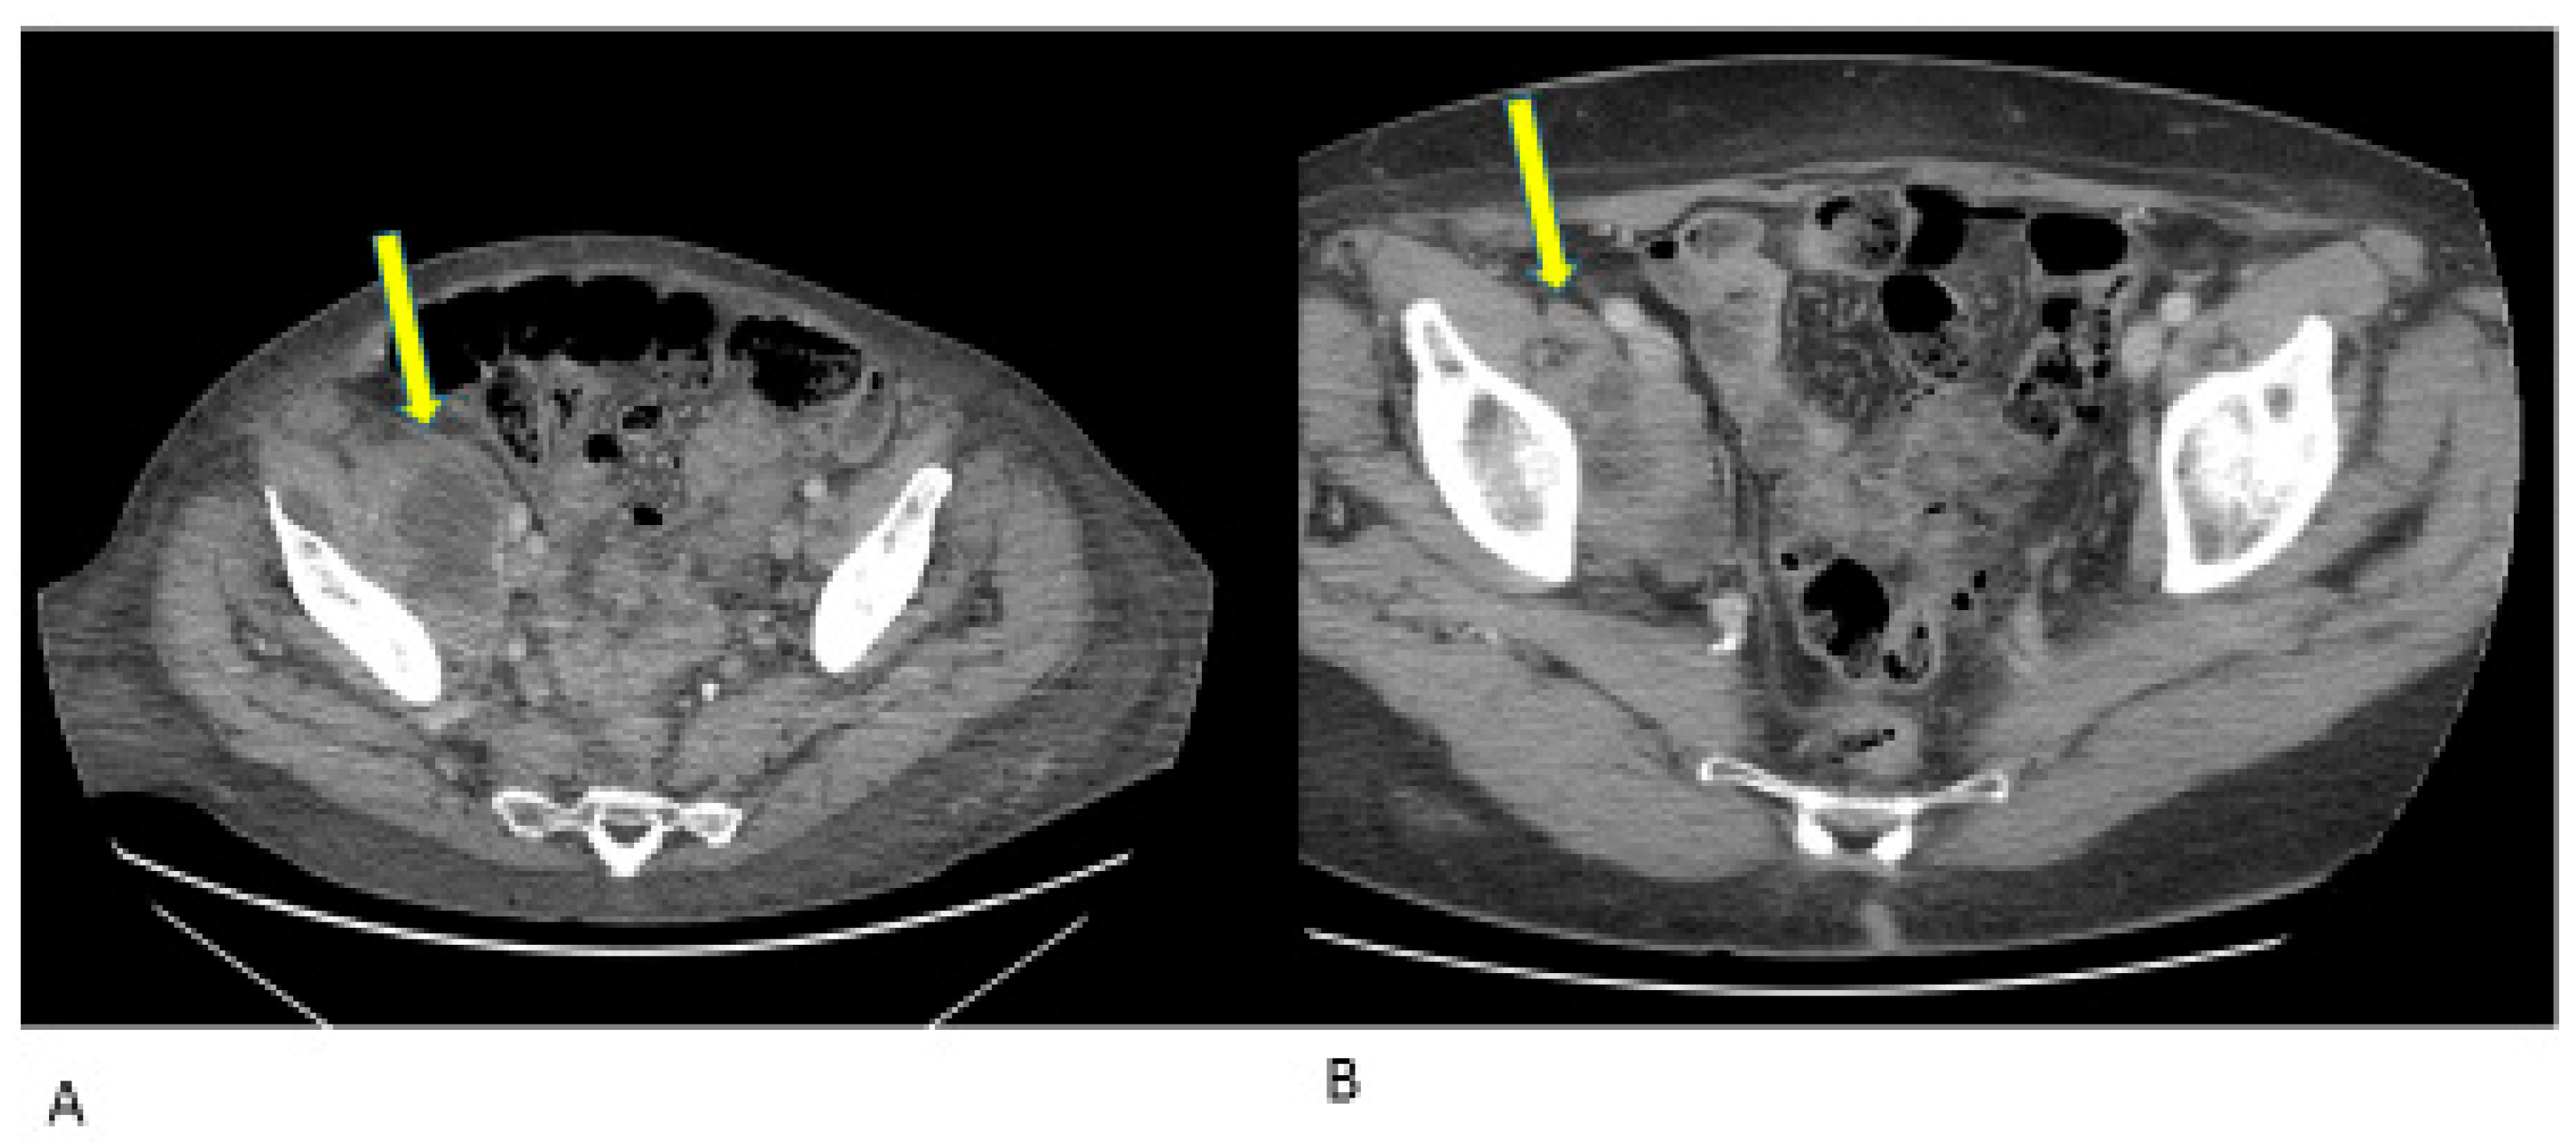

- Case 1:

- Case 2:

- Case 3:

- Case 4:

- Case 5:

- Case 6: